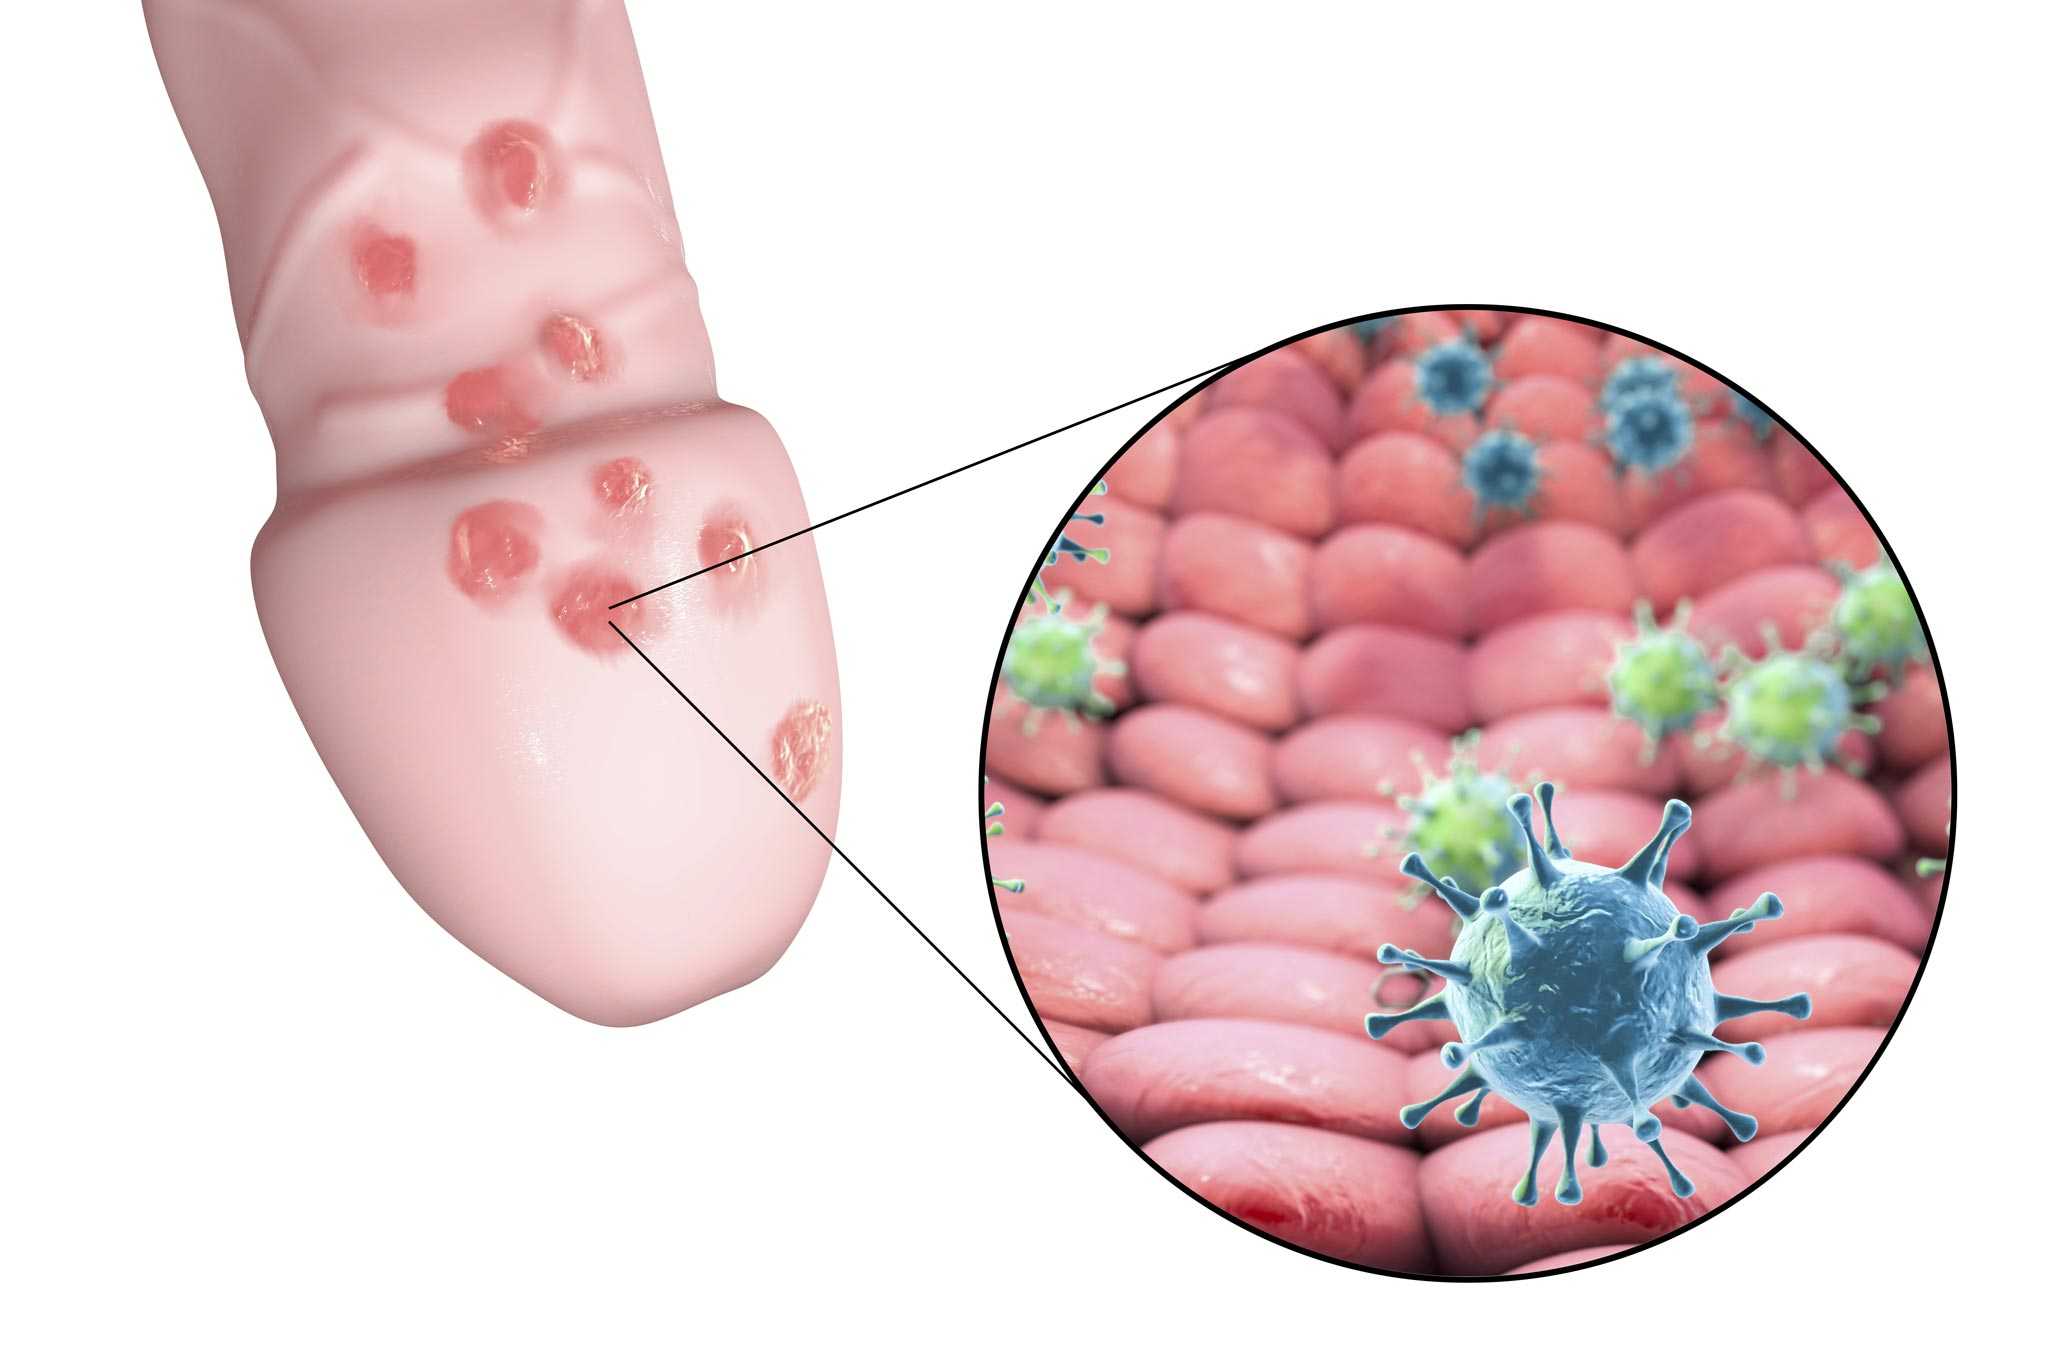

Кондиломы - это одно из самых распространенных заболеваний, передающихся половым путем. Они вызваны вирусом папилломы человека (ВПЧ) и могут появляться на внешних половых органах, анусе, ротовой полости и других областях тела.

Симптомы кондилом могут варьироваться, и визуальное представление этого заболевания может быть различным. Некоторые кондиломы выглядят как небольшие бугорки или бородавки, в то время как другие могут иметь форму плоских пятен или цветных наростов.